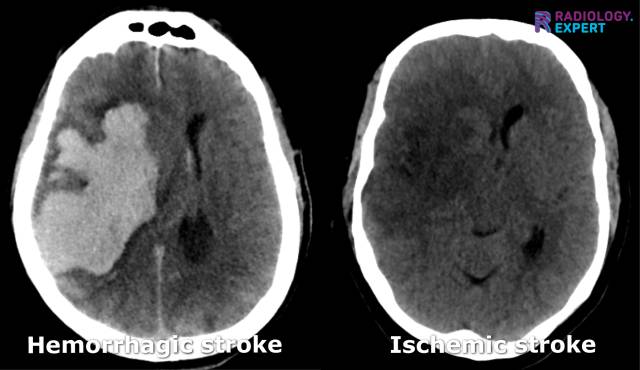

In cases of clinical suspicion of a stroke, a non-contrast CT scan of the brain is generally performed first: a 'non-contrast CT' (Fig. 12). The main objective is to distinguish between an ischemic and a hemorrhagic stroke and to rule out other abnormalities (such as space-occupying lesions). A non-contrast CT brain has a high sensitivity for detecting intracerebral hemorrhages. However, the brain parenchyma often shows few abnormalities in the first hours of a cerebral infarction. Nonetheless, there should always be a search for (subtle) CT abnormalities that may indicate ischemia. Any occlusion's presence, extent, and location are difficult to determine on a non-contrast CT scan.

Figure 12. Non-contrast CT brain. Hemorrhagic stroke vs. ischemic stroke.